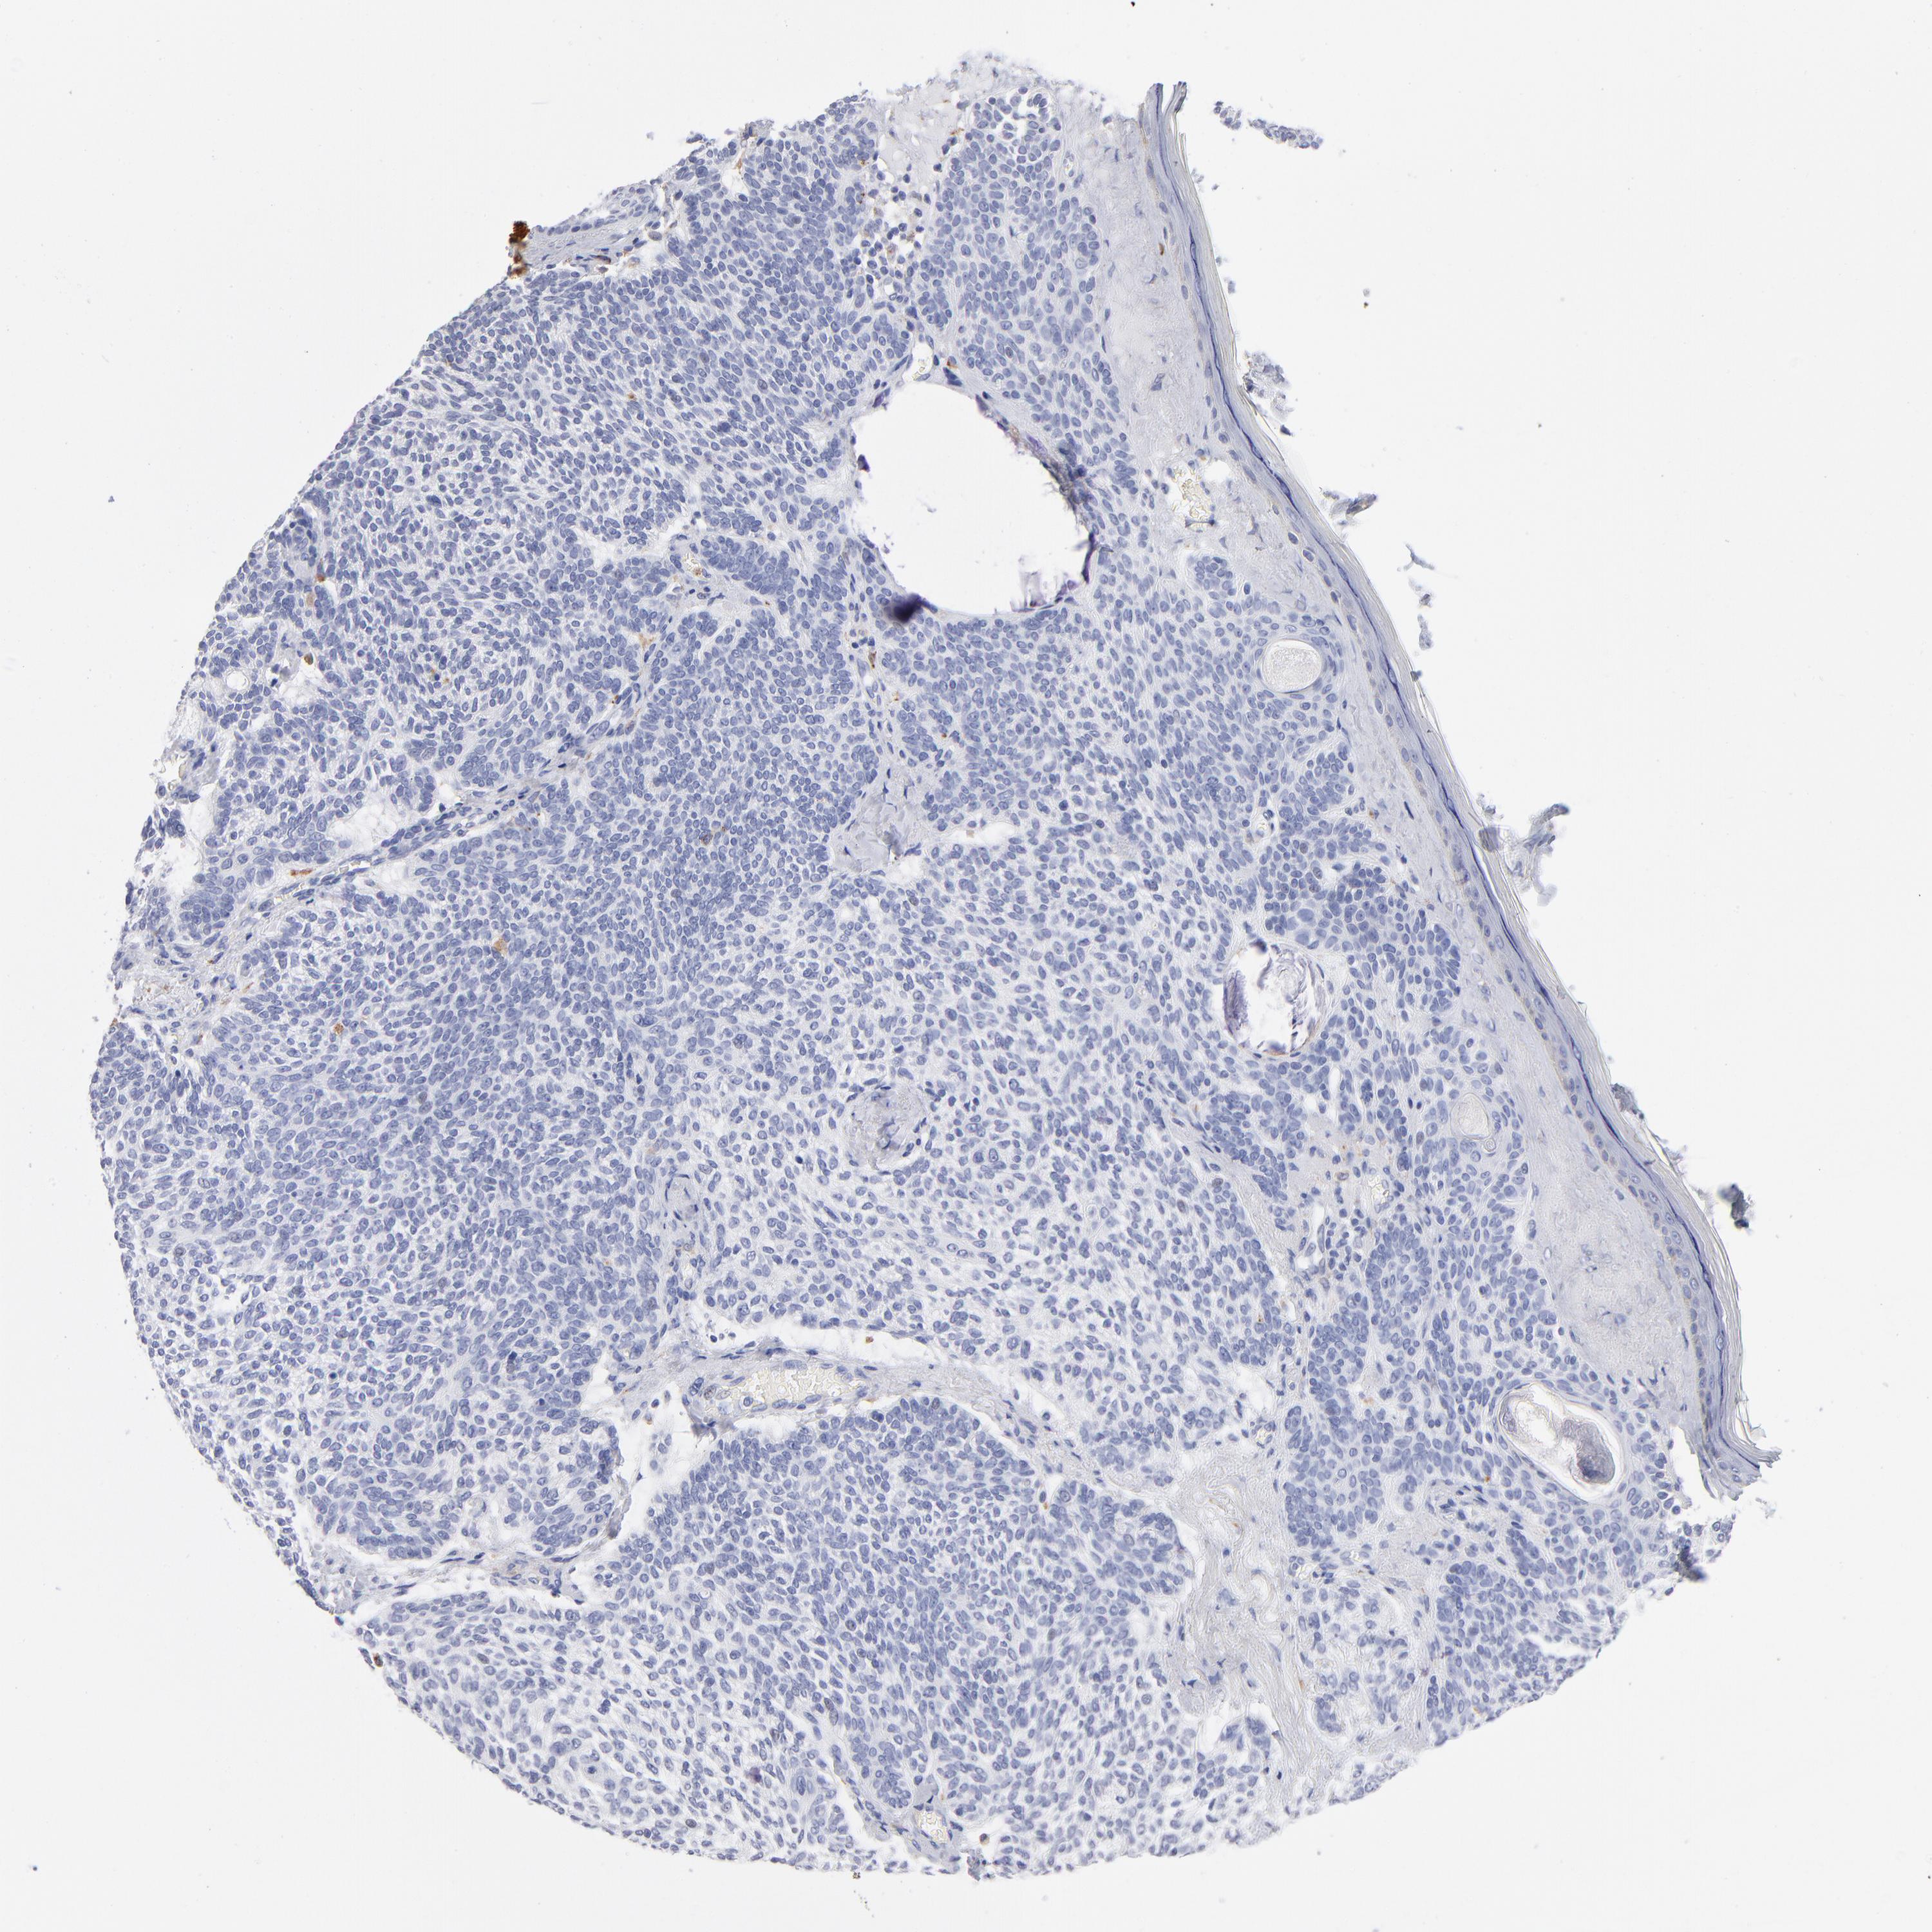

SKIN CANCER - Protein expressioni

A mouse-over function shows sample information and annotation data. Click on an image to view it in a full screen mode. Samples can be filtered based on level of antibody staining by selecting one or several of the following categories: high, medium, low and not detected. The assay and annotation is described here.

Antibody stainingi

Antibody staining in the annotated cell types in the current human tissue is reported as not detected, low, medium, or high, based on conventional immunohistochemistry profiling in selected tissues. This score is based on the combination of the staining intensity and fraction of stained cells.

Each image is clickable and will lead to virtual microscopy that enables deeper exploration of all samples and also displays staining intensity scores, fraction scores and subcellular localization as well as patient and tissue information for each sample.

Antibody HPA003740

Squamous cell carcinoma, NOS

Basal cell carcinoma